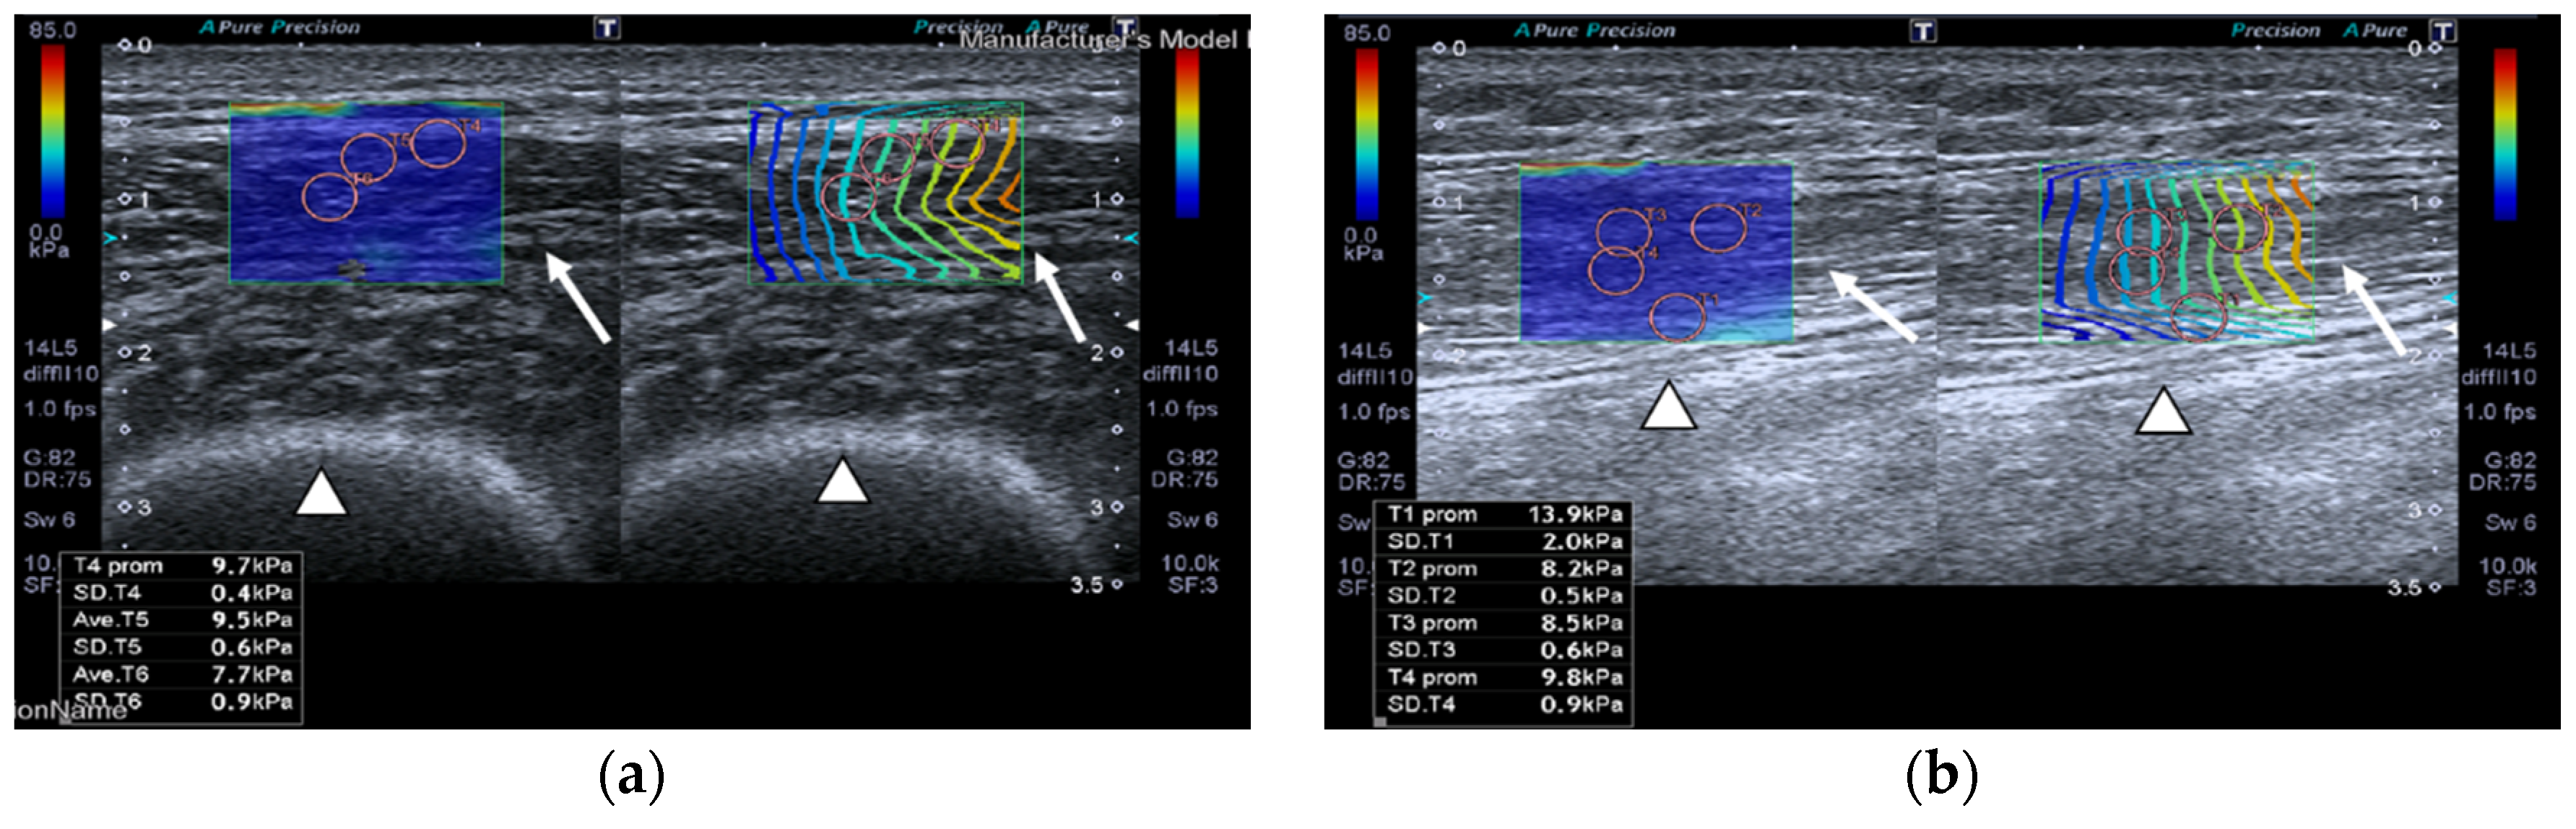

SMI images of a patient and a healthy control are displayed in Figure 2.

Transversal QRF muscle US scan and the superb microvascular imaging (SMI) built-in software that indicates microvascularization. (a)Transversal QRF muscle (arrow) US scan, femur (arrowhead). SMI image shows dot-like vessels and a penetrating vessel (star) for a matched healthy control (60 years old). (b) Transversal QRF muscle (arrow) US scan, femur (arrowhead); subcutaneous edema with intramuscular and interfacial fluid (thick arrow). SMI image shows dot-like vessels for a patient with multiorgan failure (58 years old). (c) Transversal QRF muscle (arrow) US scan, femur (arrowhead). SMI image shows minimal linear vessels for another patient with multiorgan failure (51 years old).